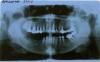

st_lena Опубликовано 24 ноября, 2010 Автор Поделиться Опубликовано 24 ноября, 2010 Спасибо за ответы. Сейчас попробую прикрепить фото. А вопросы у меня такие: 1. Возможно ли на импланты поставить мост внизу справа? 2. Достаточно ли 2-х имплантов? Если нет, целесообразно ли ставить бюгель на замках? Ссылка на комментарий

sandakov Опубликовано 25 ноября, 2010 Поделиться Опубликовано 25 ноября, 2010 1. Возможно ли на импланты поставить мост внизу справа? 2. Достаточно ли 2-х имплантов?Вертикального объема кости достаточно, про горизонтальный трудно судить, если уж не совсем истончена кость в области предполагаемой имплантации, то вполне можно поставить. имплантов лучше ставить 3 и соответственно мост делать более длинной протяженностью. А про бюгель могу сказать что скорее всего конструкцию на кламмерах носить не будете, под замковый надо бы еще один зуб обработать и получается что два крайних зуба будут закрыты коронками, что, учитывая расположение дефекта не больно то эстетично и практично. Ссылка на комментарий